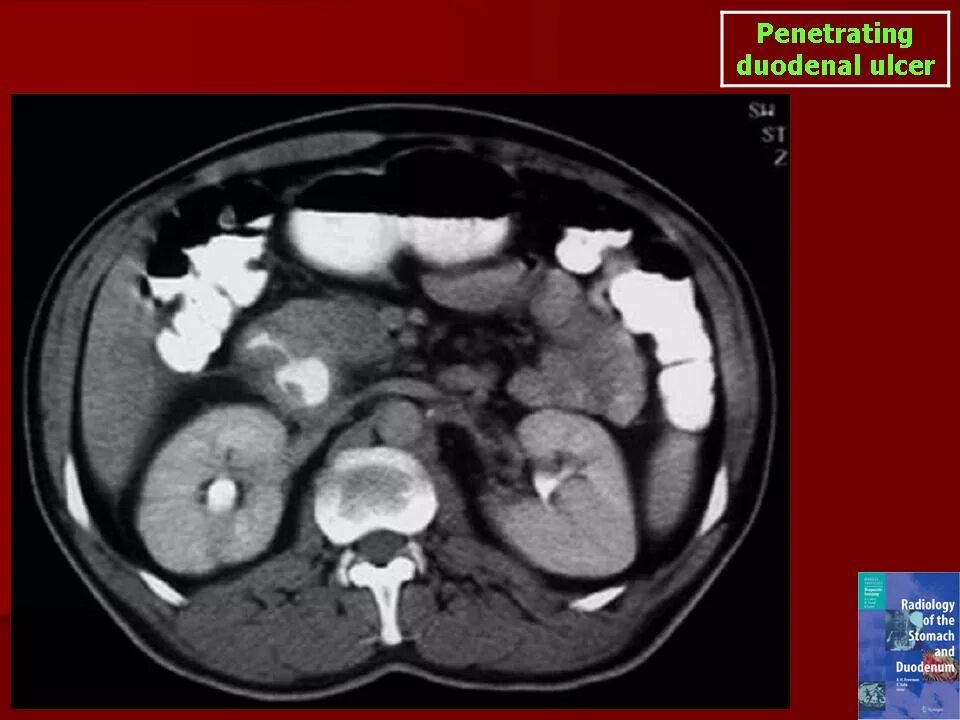

Язва желудка кт